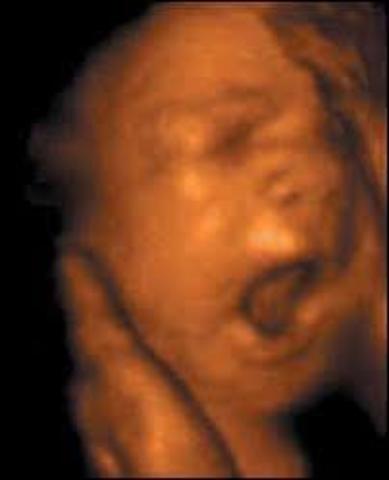

El bebé puede bostezar y hacer gestos faciales. Es posible que se sientan algunos movimientos del bebé porque empieza a patear y mover las manos con más fuerza. Sus ojos y orejas ya alcanzan su ubicación definitiva por esta semana.

El estómago empieza a funcionar el bebé traga fluido del líquido amniótico para ejercitar el aparato digestivo.

Además, los huesos del oído interno y las terminales nerviosas del cerebro se han desarrollado lo suficiente.Tendrá unos 14 centímetros y 150 gramos.

A partir de este momento, el bebé ya puede oir. Aunque escucha de forma distorsionada, puede reconocer el latido del corazón o la respiración. Los movimientos del bebé en esta semana aún son reflejos.

El bebé madura rapidamente, especialmente su cerebro, que cuenta ya con más de 30.000 millones de neuronas.La forma y las proporciones generales del bebé son completamente humanas.

El bebé mide aproximadamente 16 cm largo y pesa cerca de 255 gramos